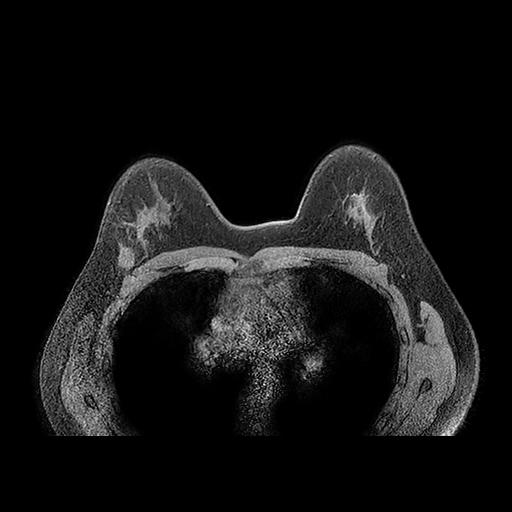

To close off this day, I also did a magnetic resonance imaging (MRI) exam with a contrast medium. The question to answer here was mainly: is my tumor a solitary lesion? or part of a bigger, scattered group? and how big is it? are my axillary lymph nodes healthy or not? This is the imaging modality for dense breast imaging: it’s also, unfortunately, very expensive.

The doctors panicked here a little bit, as the MRI showed weird inflammatory activities around my axillary zones: it turned out this was due to the double shots of vaccine I had 24 hours before (both for COVID and for the seasonal flu). Admittedly not a great timing, but I needed to help my immune system as fast as possible before starting chemotherapy. Yes, those up there are my boops as I breathe in and out on the machine. The exam was long, uncomfortable, and loud as hell.